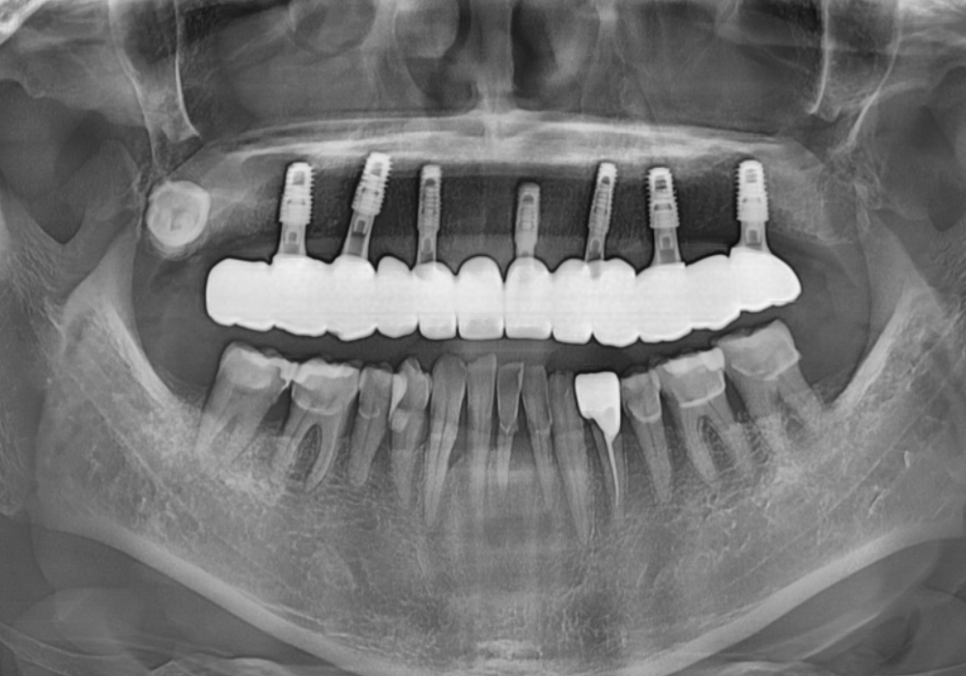

마침내 완성된 보철물을 끼워 드린 날!

기우뚱거리던 틀니를 벗어버리고,

이제는 내 치아처럼 편안하게

식사하실 수 있게 된

환자분의 모습을 보니

저도 참 뿌듯했는데요~

251111

사실 틀니의 불편함에서

하루빨리 벗어나고 싶은 환자분께

5개월이라는 기다림은

결코 짧은 시간이 아니었을 거예요.

250531(전) 251111(후)

하지만 잇몸에 얹어 쓰는 틀니와 달리,

내 뼈와 임플란트가 단단히 하나가 되는 과정은

'진짜 내 치아' 같은 힘을 얻기 위해

반드시 거쳐야 하는 시간입니다.

조금 느린 것 같아도 이 원칙을

지키는 것이야말로,

다시는 기우뚱거리는 틀니로 돌아가지 않는

가장 확실하고 안전한 지름길이 되어줄 것입니다.